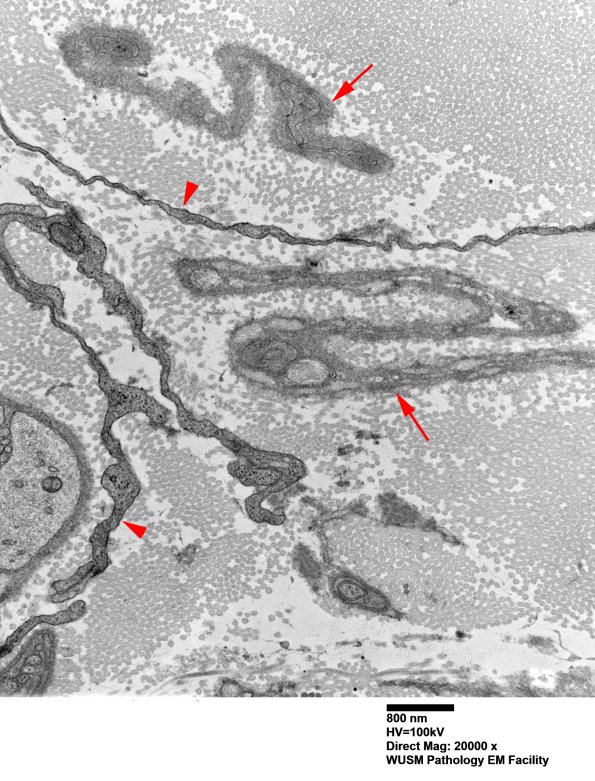

I think these are either fibroblast processes (arrowheads) or atrophic Schwann cell processes (arrows). (electron micrographs)